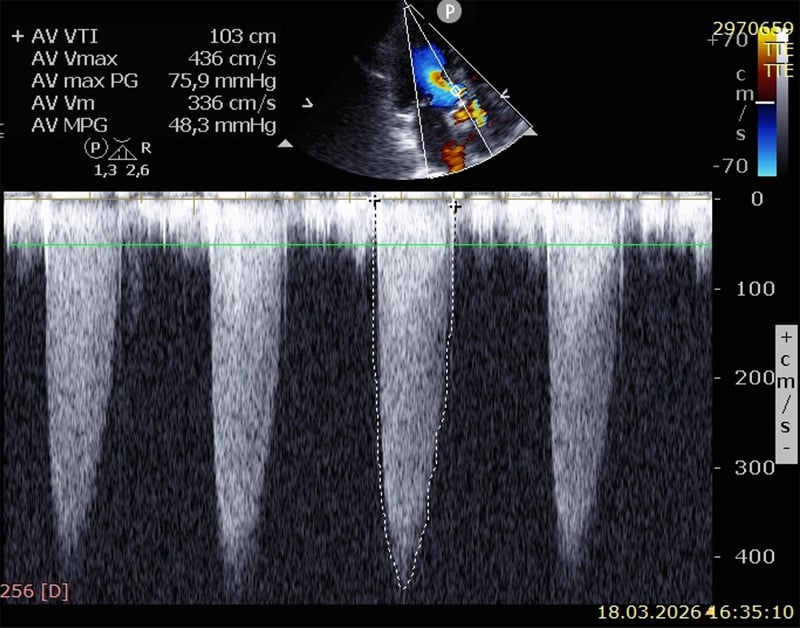

Echocardiography

- Normal systolic left and right ventricular function (EF ~ 65%)

- Moderate concentric hypertrophy

- High-flow aortic valve stenosis (maximum gradient 76 mmHg, mean gradient 48 mmHg, no aortic valve insufficiency)

- Grade I mitral and tricuspid valve insufficiency

- Estimated pulmonary artery pressure ~ 25 mmHg